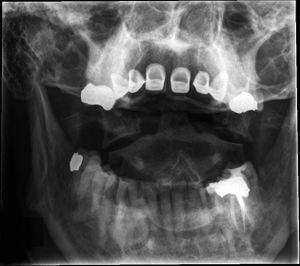

- Fracture of the anteterior and posterior arches[1]

- Due to axial loading transmitted through occipital condyles to the lateral masses

- Lateral x-ray: Increase in the predental space between C1 and dens (>3mm in adults, >5mm in children)

- Odontoid x-ray: Masses of C1 lie lateral to outer margins of articular pillars of C2

- If either of the above findings on x-ray obtain CT C-spine